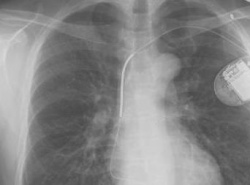

"»ðÀÔÇü Á¦¼¼µ¿±â, Àå±âÀû ºÎÀÛ¿ë À§Çè" (¼¿ï=¿¬ÇÕ´º½º) ÇѼº°£ ±âÀÚ = ½ÉÀå¹Úµ¿ÀÌ °©ÀÛ½º·´°Ô ºÒ±ÔÄ¢ÇØÁú ¶§ À̸¦ °¨Áö, Àü±âÃæ°ÝÀ» °¡ÇÔÀ¸·Î½á ½É¹Úµ¿À» Á¤»óÀ¸·Î ȸº¹½ÃŰ´Â »ðÀÔÇü Á¦¼¼µ¿±â(implanted def...